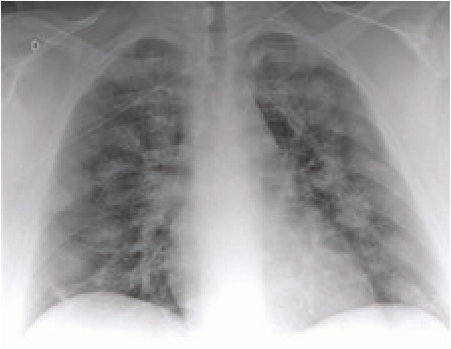

Hallazgos Radiologicos De 81 Pacientes Con Neumonia Por Covid 19 En Wuhan Covid 19 Intramed

www.intramed.net

Radiografias De Torax A Traves De Vidrio En Pacientes Con Covid Everything Rad

www.carestream.com

Coronavirus Los Rayos X Muestran La Forma En Que La Infeccion Por Covid 19 Destruye Los Pulmones Observatorio Regional De Tuberculosis De Las Americas

actbistas.org